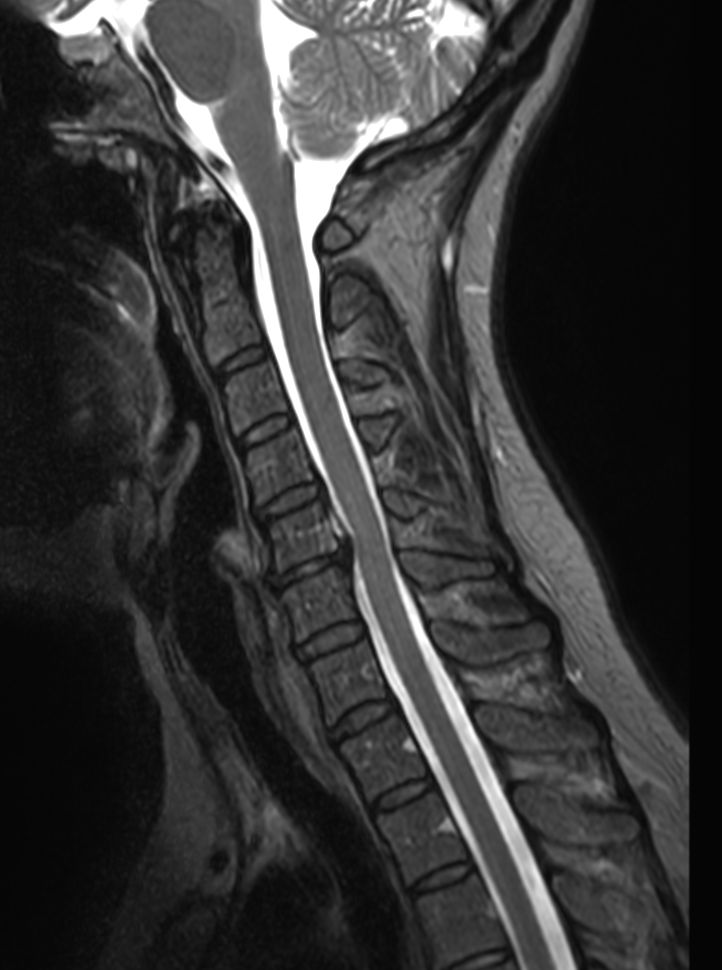

Sagittal T2w TSE mDIXON XDIn phase

Sagittal T2w TSE mDIXON XDPartial FatSat

Sagittal T2w TSE mDIXON XDWater only